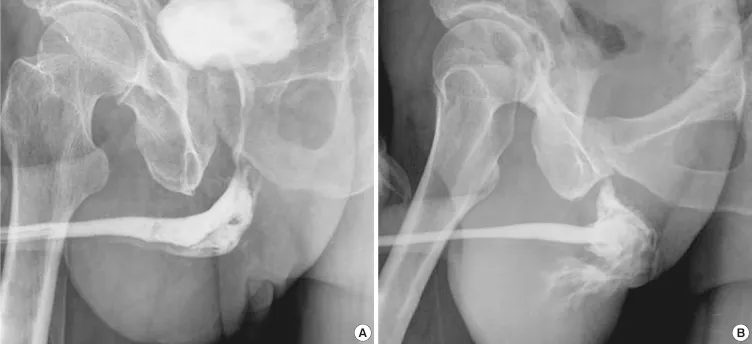

- Urethral Injury:

- Types: Posterior (pelvic #; prostatomembranous), Anterior (straddle; bulbar/pendulous).

- Signs: 📌 BUMPH (Blood at meatus, Unable to void, Meatal/perineal swelling, Pelvic fracture, High-riding prostate).

⭐ Blood at the urethral meatus is a cardinal sign of urethral injury; perform Retrograde Urethrogram (RUG) before catheterization.

- Management:

- Partial tear: Suprapubic cystostomy (SPC) or gentle catheter. Early endoscopic realignment possible.

- Complete tear: SPC, then delayed repair (3-6 months). Early endoscopic realignment also an option.

- Complications: Stricture, incontinence, impotence.